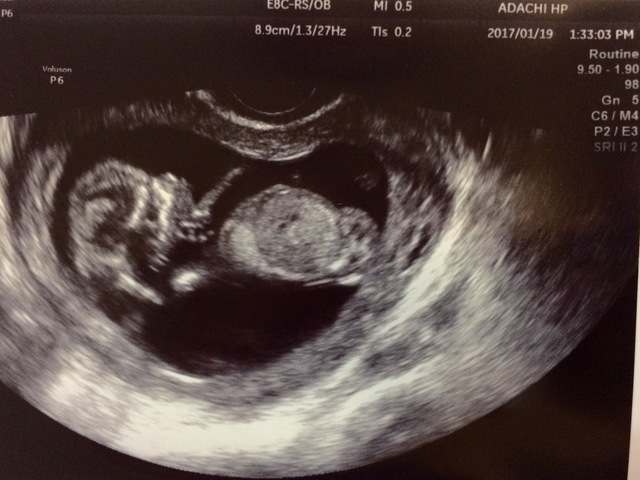

13週2日(13w2d・男の子)|ゆちゃむ さん(24歳)

エコー写真撮影時のエピソード:

初めて正面で見れて全体が写ったエコーでした。旦那と男の子っぽいねと予想してました。じいじばあばにもエコー見せて最近のは凄いねと話しで盛り上がってました。

まだお腹がそんなに出てなかったから実感が薄かったけどこのエコー見て実感が湧きました。